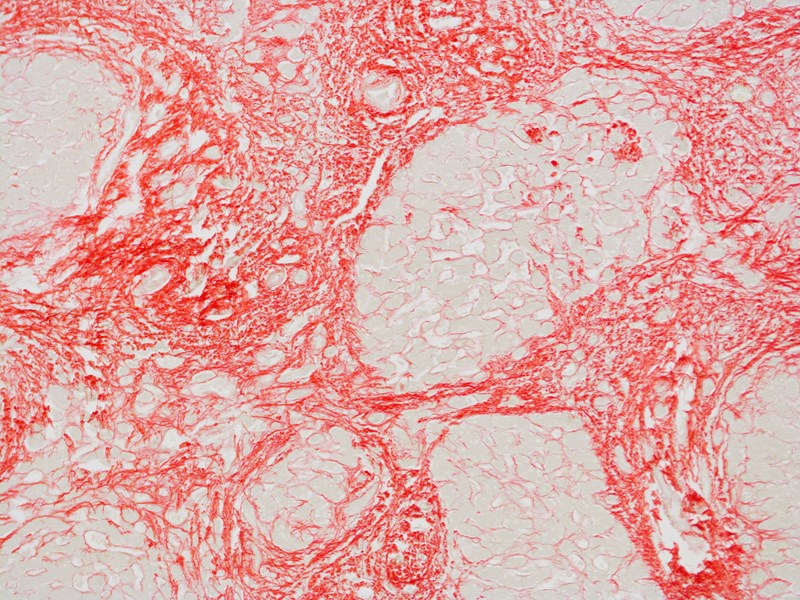

In excess of 1 million people die annually as a consequence of liver cirrhosis which is the end-stage of fibrotic liver disease.

Cirrhosis results from progressive fibrosis caused by over 100 different types of liver diseases affecting all age groups and ethnicities.

At present, there are no clinically approved medicines that directly halt or reverse the fibrotic process that leads to cirrhosis.